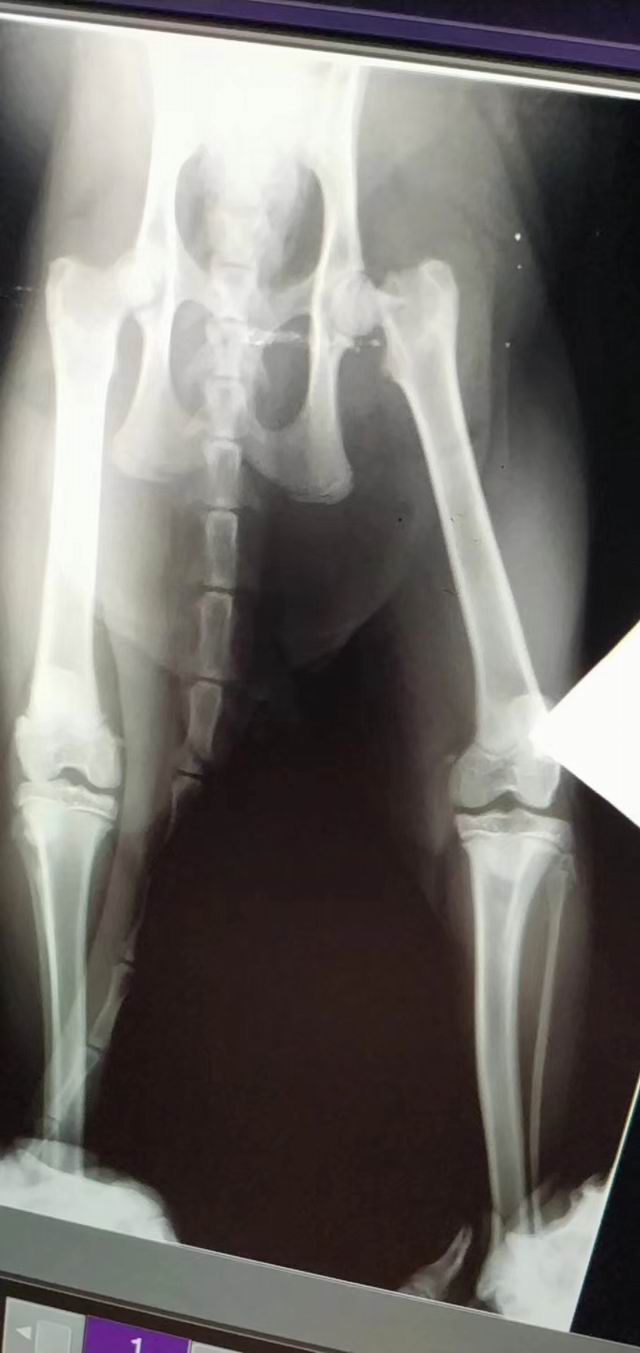

一例股骨手術(shù)順利完成

一例股骨手術(shù)/順利完成(ok)

桔子,橘貓,1歲齡,因外力導(dǎo)致股骨斷裂/嚴(yán)重跛形/不敢受力,主人帶至醫(yī)院實施手術(shù)矯正,進(jìn)囗麻藥+手術(shù)順利(ok),住院護(hù)理中……靜待恢復(fù)于往常